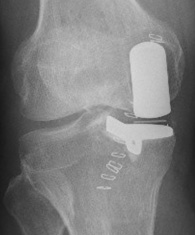

很多人到了六七十歲,最先感到疼痛的就是膝蓋。大家可能都聽說過人工膝關節置換手術。但其實,關節置換手術又分為「全膝關節置換手術」和「單髁膝關節置換」,單髁膝關節置換比起全膝關節置換手術,有創傷更小、恢復更快的優勢。

單髁置換怎樣做?

單髁置換就像給膝蓋「補牙」——僅替換磨損的軟骨和少量骨質,保留健康組織和韌帶。